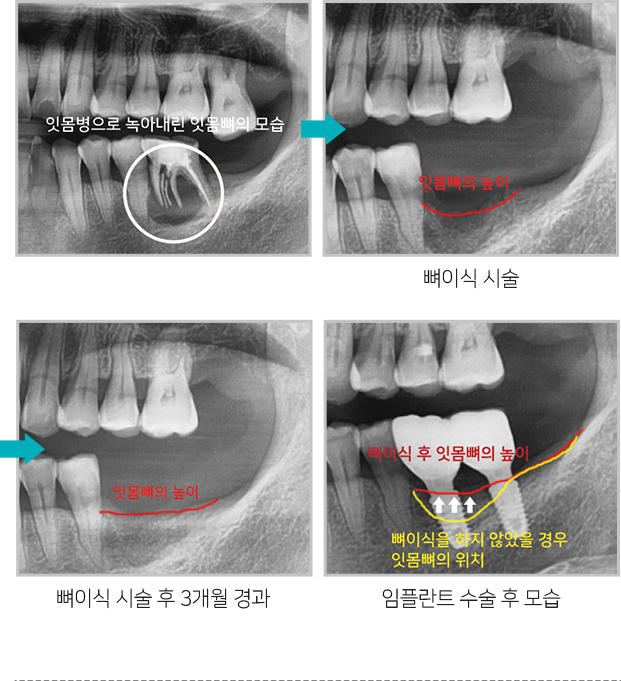

뼈이식 시술 후 잇몸뼈의 위치 변화

치조골은 치아를 발치 한 후 지속적으로 녹아

없어지는데 치조골을 보존하기 위해

발치 후

미리 뼈이식 하면 추후 임플란트 식립시 충분한

치조골을 확보할 수 있어

임플란트 수술을 하는데

매우 유리합니다.